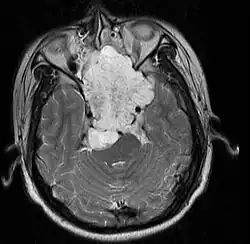

| MRI of extensive clival chordoma in 17-year-old male patient, axial view. Tumor in the nasopharynx extending from nasal cavity to brainstem posteriorly is clearly visible. | |

Chordoma is a rare slow-growing neoplasm (cancer) that arises from cellular remnants of the notochord in the bones of the skull base and spine. The evidence for the notochordal origin of chordoma is the location of the tumors (along the neuraxis), the similar immunohistochemical staining patterns, expression of brachyury, and the demonstration that notochordal cells are preferentially left behind in the clivus and sacrococcygeal regions when the remainder of the notochord regresses during fetal life.

In layman's terms, chordoma is a type of bone cancer, and is classified as a sarcoma.[1] Chordomas are sometimes mistakenly referred to as a brain, brainstem or spinal cord tumors due to their location near those critical structures, but they are not derived from nervous tissue.